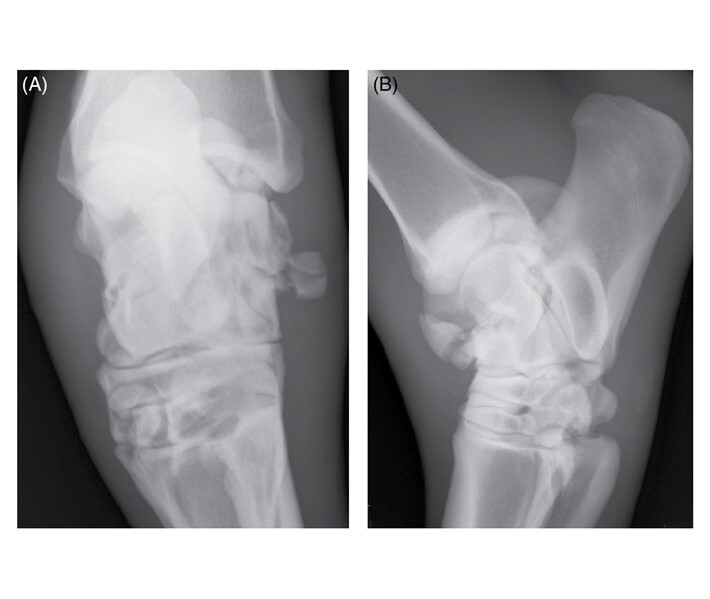

distal intermediate ridge of the tibia (DIRT) (Figure 99-24, A),

followed by the lateral trochlear ridge of the talus (see Figure 99-24, B),

Figure 99-24. (A) DMPLO radiographic view of the tarsus showing a distal intermediate ridge of the tibia OCD lesion. (B) DMPLO radiographic view of the tarsus showing a large lateral trochlear ridge OCD lesion.